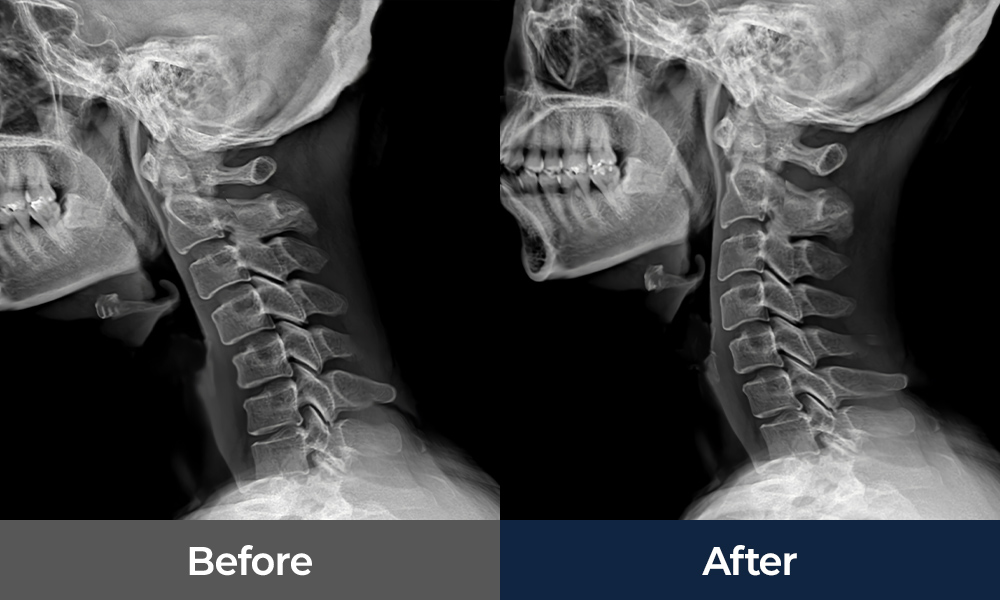

• 목디스크

• 일자목/거북목

척추 질환에 적용되는 비수술 치료

• 체외충격파

• 신경증식치료

• 신경차단술

• 교정도수치료